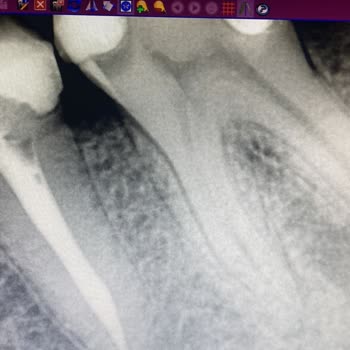

Helal etmiyorum yaşadığım sıkıntıyı asla. Buraya yazıyorum çünkü bıktık artık insanların sağlığımızı tamamen ticari görüp ona göre yaklaşan insanlardan. Bundan 3 ay önce dent dream klinik doktor *** diş tedavilerimi yaptırdım. Sol alt dişimde ilk günden beri bir sızı vardı fakat iyileşme sürecini dü...